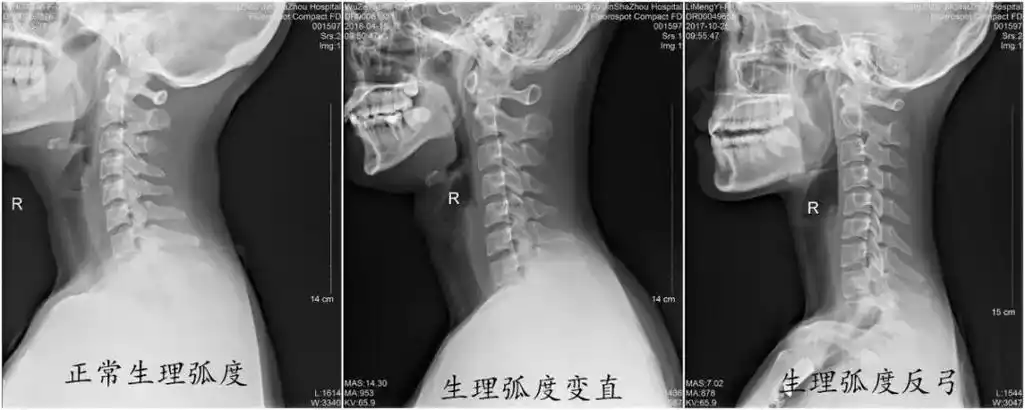

为什么颈椎生理曲度会变直会有什么严重后果吗